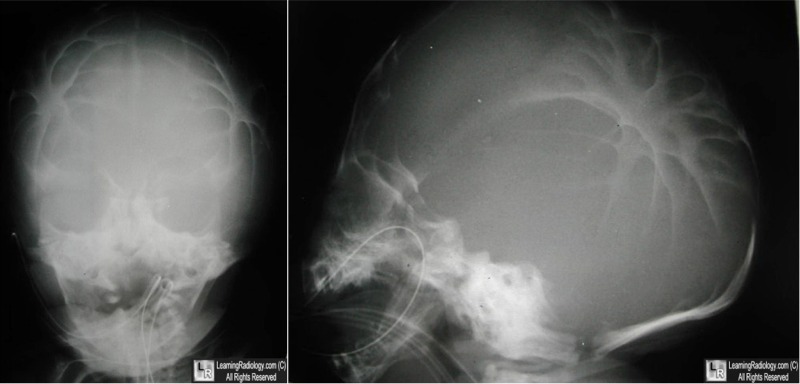

Lacunar Skull

Luckenschadel Skull

- Bone dysplasia of skull consisting of multiple oval lucencies separated by dense, bony ridges

- Associated with

- Neural tube defects, especially myelomeningocele

- Chiari II malformation

- Encephalocele

- Not related to degree of concomitant hydrocephalus

- Inner table more affected than outer

Imaging Findings

- Well-defined lucent areas in calvarium representing nonossified fibrous bone

- Lacunae are bounded by normally ossified bone

- Most prominent in parietal bones

- Small posterior fossa associated with Chiari II malformation

Lacunar Skull. There are multiple focal areas of radiolucency in the skull (white arrows)

bounded by more normal, dense bony ridges. The child had a known myelomeningocele.

Luckenschadel. This newborn skull is markedly dysplastic with little in the way of normal, dense bony ridges.